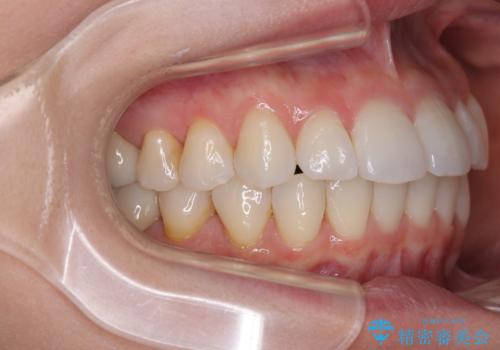

- 前歯のデコボコや、やや突出した感じを気にして来院された患者様です。

抜歯矯正を必要とするほど口元の突出感はなく、本人もそこまでは気にしていない様子でした。

お仕事柄、マウスピース装着は困難とのことで、表側のワイヤー矯正にて治療を行うこととしました。

デコボコ解消の際に、前歯が前突するリスクがあったため、舌突出癖の改善と、アンカースクリューによる加強固定を行うこととしました。

矯正治療後には奥歯の銀歯やむし歯をセラミックやゴールドにて治療を行い、大変整った口腔環境へと改善さ。れました